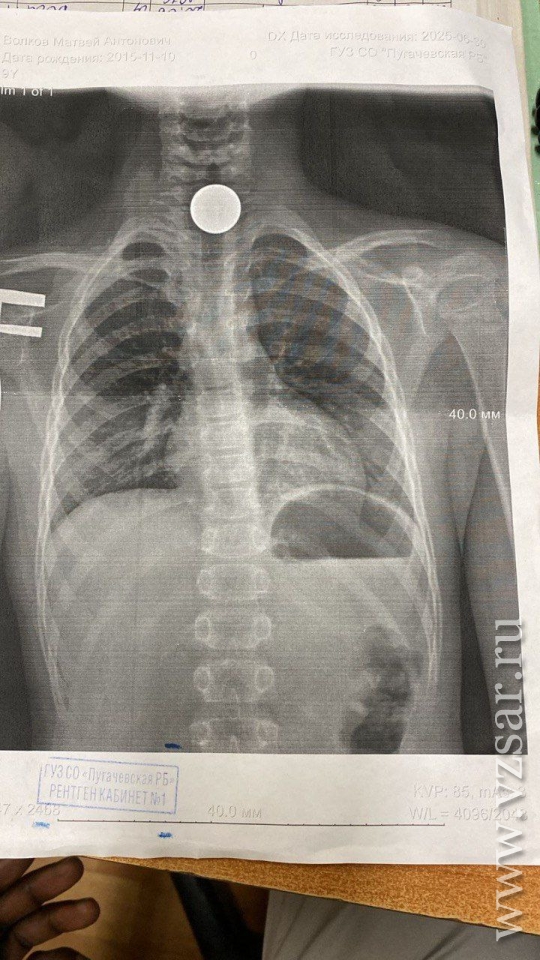

По словам ребенка, он случайно проглотил 5-рублевую монету, что подтвердил рентгеновский снимок. Однако оказалось, что мальчик "пообедал" не одним, а двумя пятачками.

"Безотлагательно была проведена малоинвазивная процедура по извлечению инородных тел. Под наркозом врач эндоскопист Репина Татьяна Владимировна и заведующий отделением, анестезиолог Кривобок Вера Васильевна достали из желудка школьника две пятирублевые монеты. В данный момент ребенок находится в стационаре. Его здоровью ничего не угрожает", - рассказали медики.